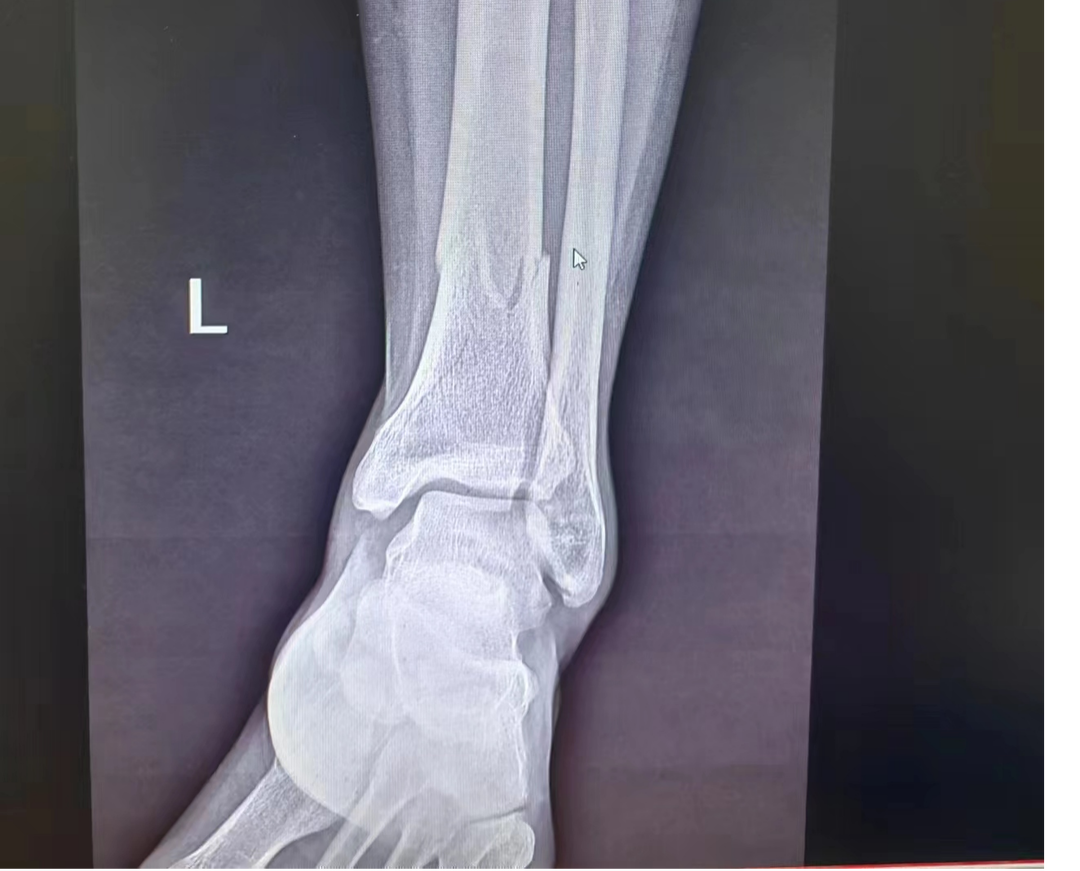

在确认孩子脱离危险后,邓喜忠被村民及时送往医院。经检查,邓喜忠左腿下段骨折移位,如果手术治疗,需要三万多元的医疗费用。面对高额的医疗费用,邓喜忠想到自己这段时间不能外出工作,家里没有了收入来源,家里还妻子和三个孩子,于是放弃了手术治疗。“当时,他的腿一点也不能动,怕我担心,还一直安慰我说没事……”妻子邓小连眼含泪花地说。

△图为邓喜忠拍片图片,经检查,邓喜忠左腿下段骨折移位

“家里确实不太宽裕,三万块钱对我们家来说是个‘大数目’了,听亲戚介绍说常宁那边有个中医可以治疗,费用低一些,就决定去那边看看。后来那个医生问得知我受伤的原因,还给我免去了不少费用。”邓喜忠说道。